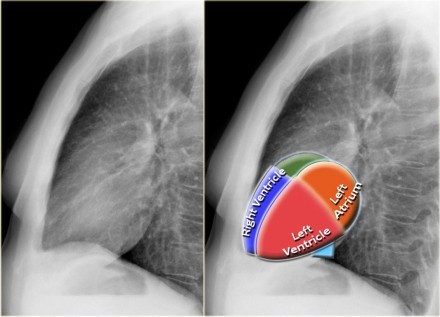

What is the normal carinal angle?

70 degrees +/- 10 degrees in adults